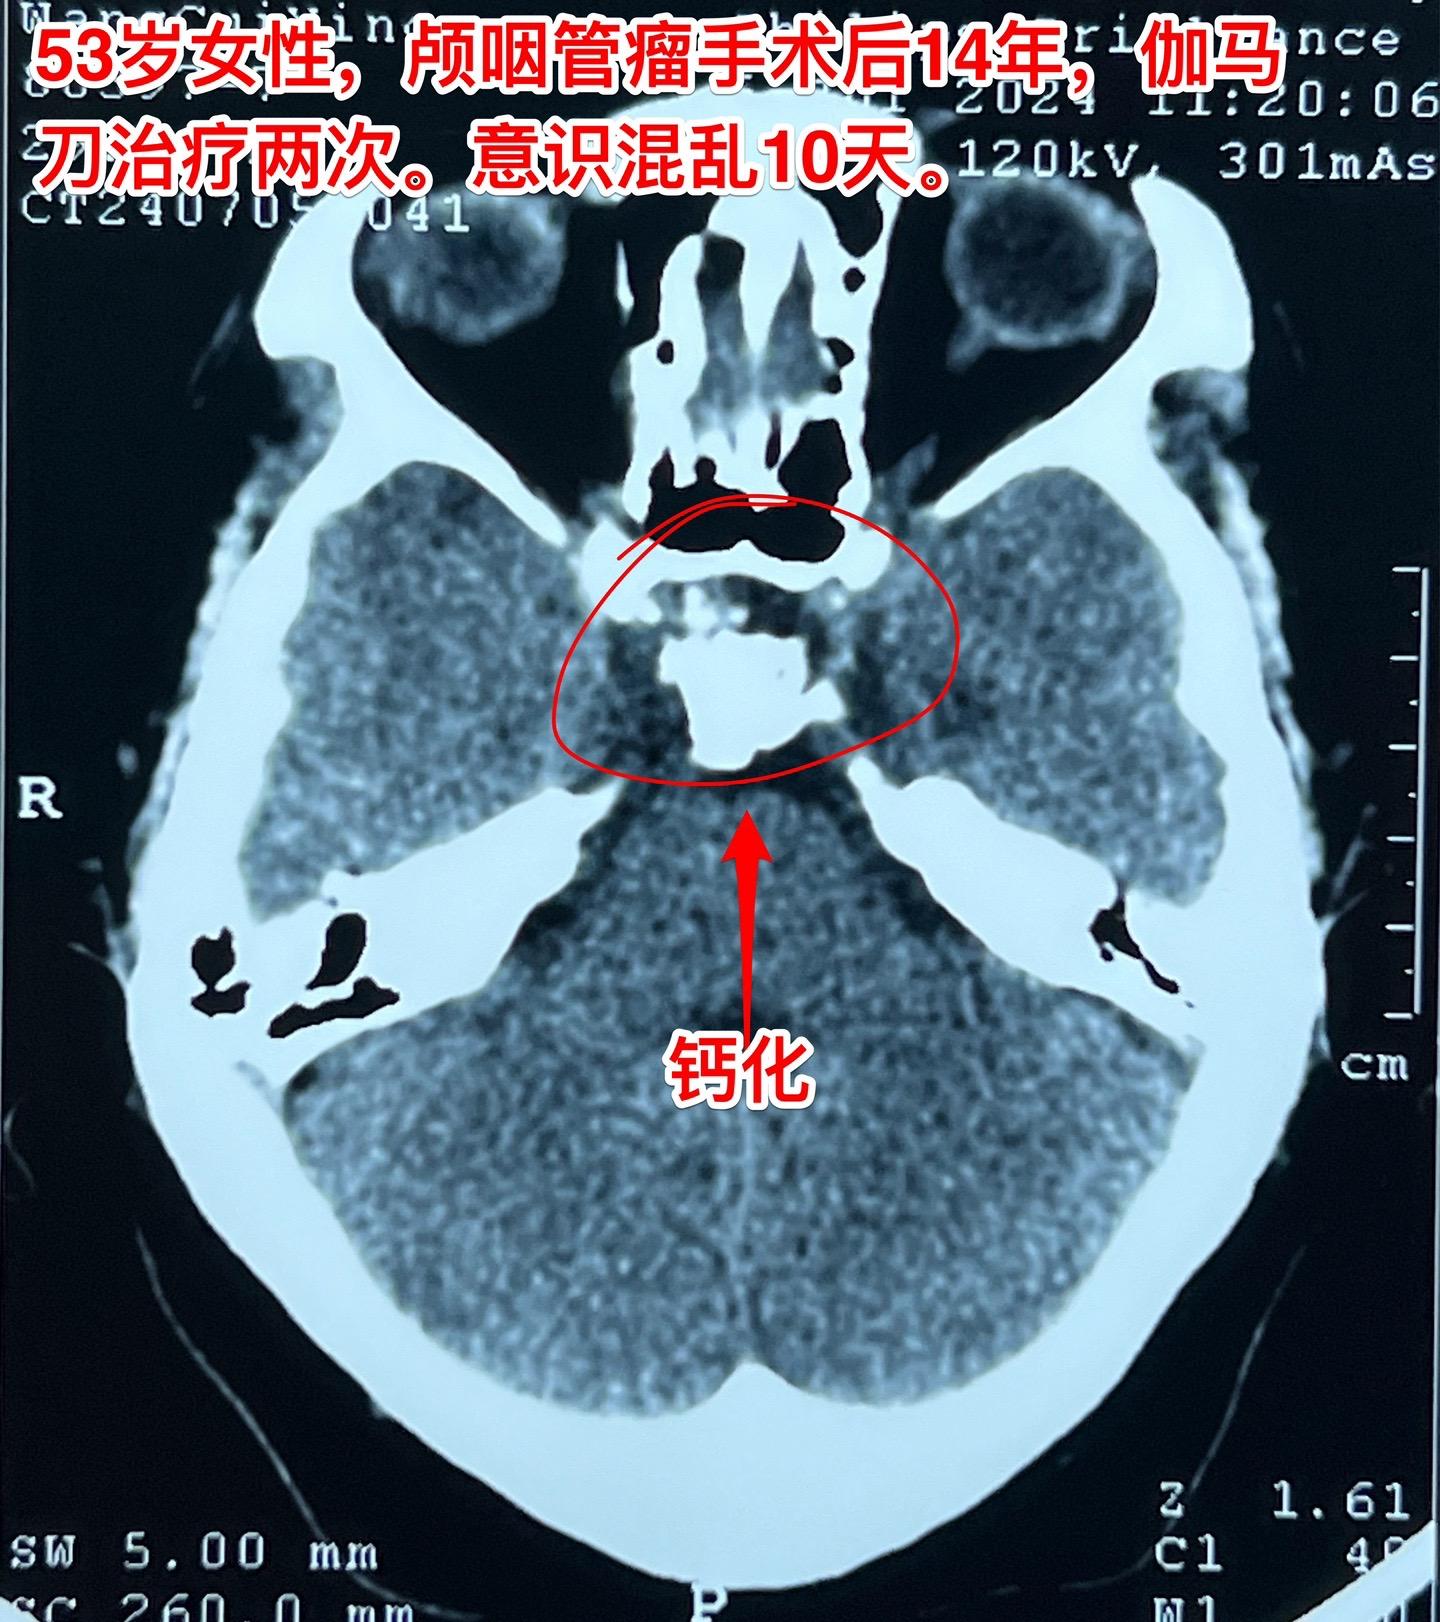

颅咽管瘤复发了怎么就意识混乱了?安徽省宿州的女性,53岁,14年前曾经作过颅咽管瘤切除手术。近10天她突然出现意识混乱,胡说,尿失禁,行走不稳。这是为什么呢? 其实她的病并不突然。 14年前作过颅咽管瘤切除手术,肿瘤有残留,就作了伽马刀治疗。2015年肿瘤复发了,又作了一次伽马刀治疗。之后生活质量还不错,能够作家务。 住院前10天她突然出现意识混乱,胡言乱语,同时还有尿失禁,行走困难。到医院去作头C T检查,发现肿瘤复发了,而且还造成了脑积水。